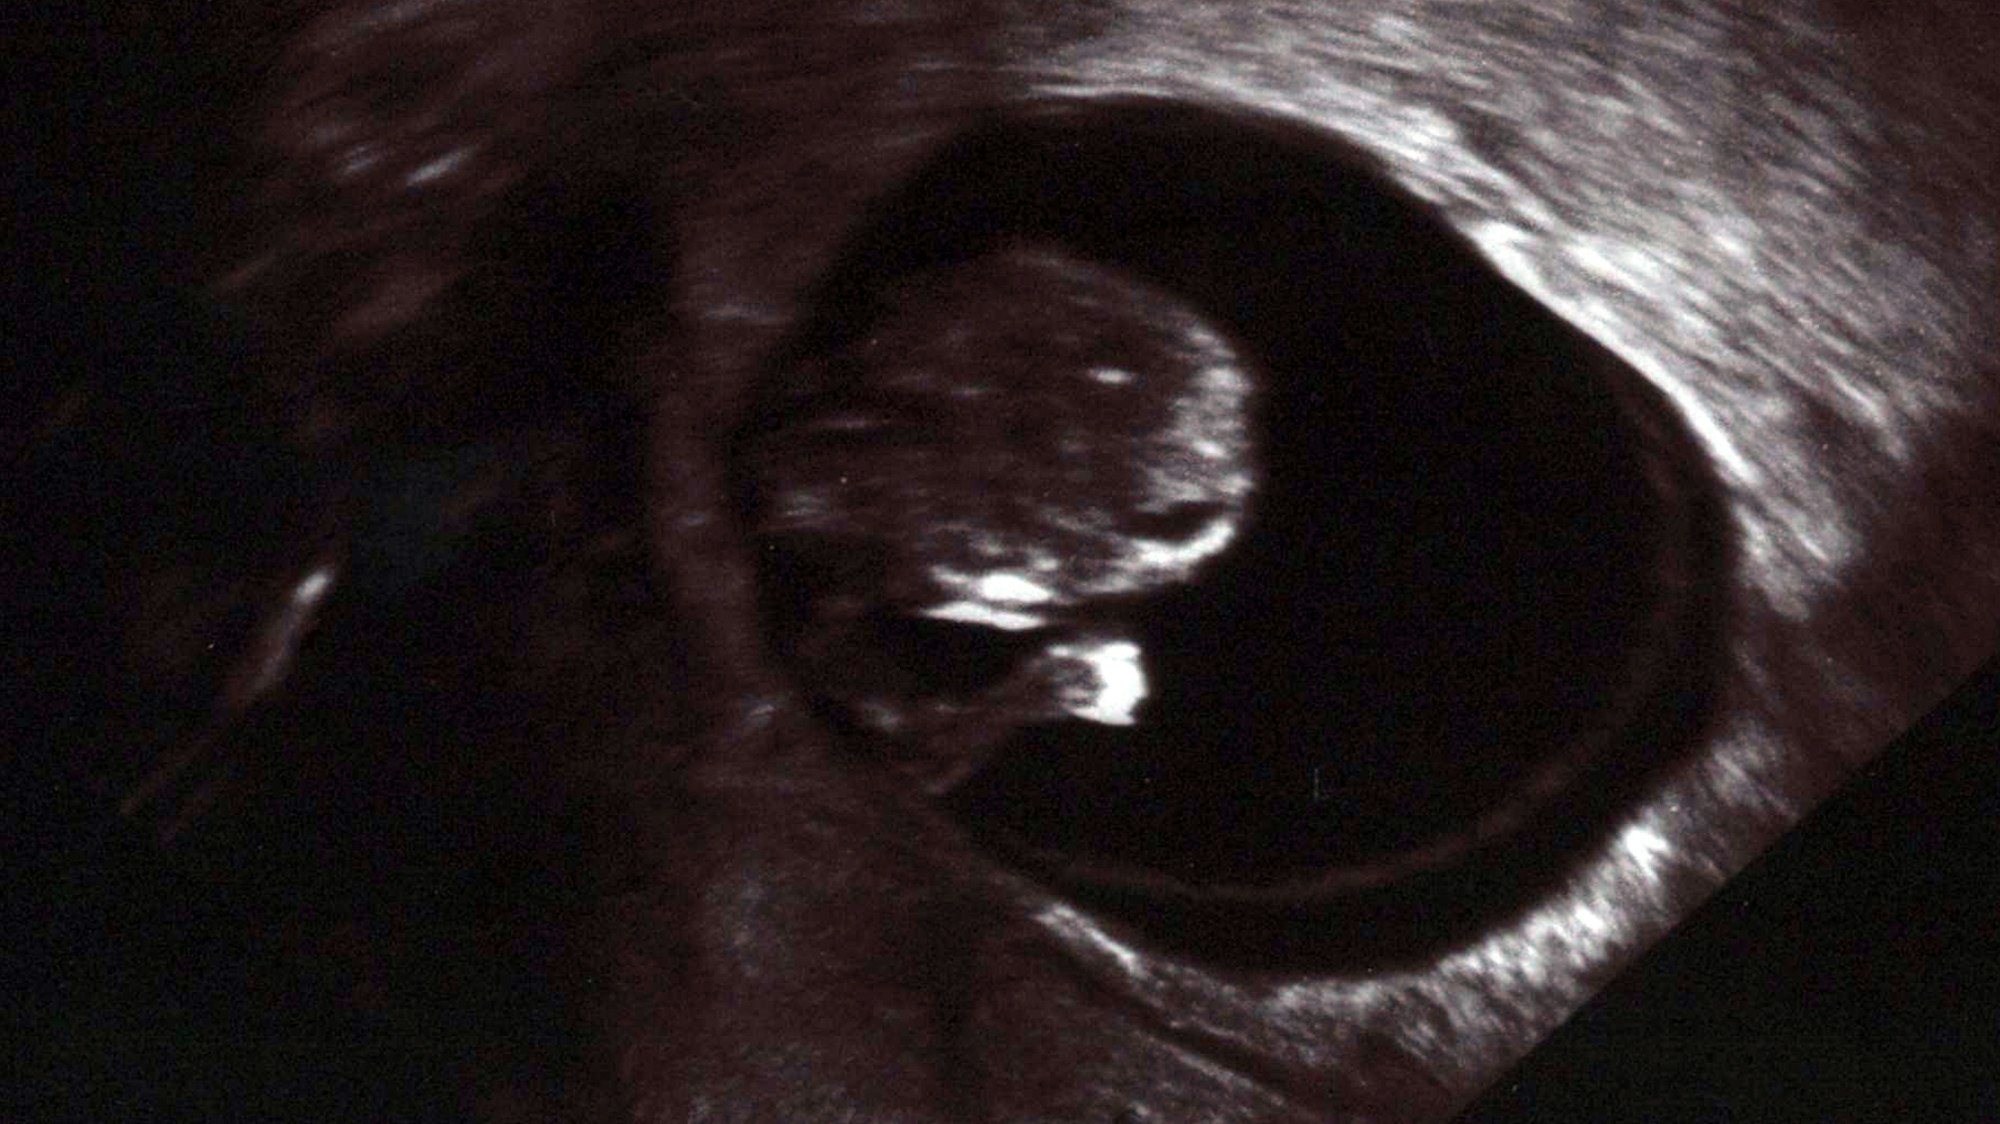

Copyright: dpa-tmn

Schon in der 10. Woche ist das Ungeborene deutlich zu erkennen und man kann seinen Herzschlag auf dem Ultraschallgerät sehen.